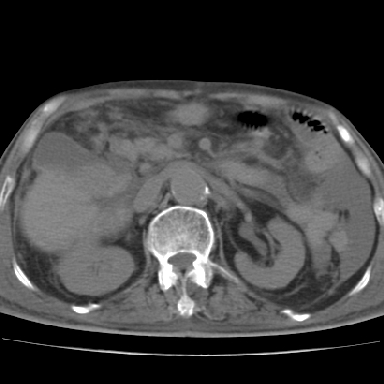

以下是引用qian在2006-12-4 19:11:00的发言:[br]胸腔和腹腔内均见有液性影,肝上极包膜下有一较大椭圆形低密度影,密度均匀,边缘清晰,结合病史考虑术后肝脓肿并胸腹腔积液。

以下是引用dyqct在2006-12-4 19:54:00的发言:[br]考虑:1、肝包膜下脓肿;[br] 2、少量腹水;[br] 3、右侧少量胸膜腔积液。